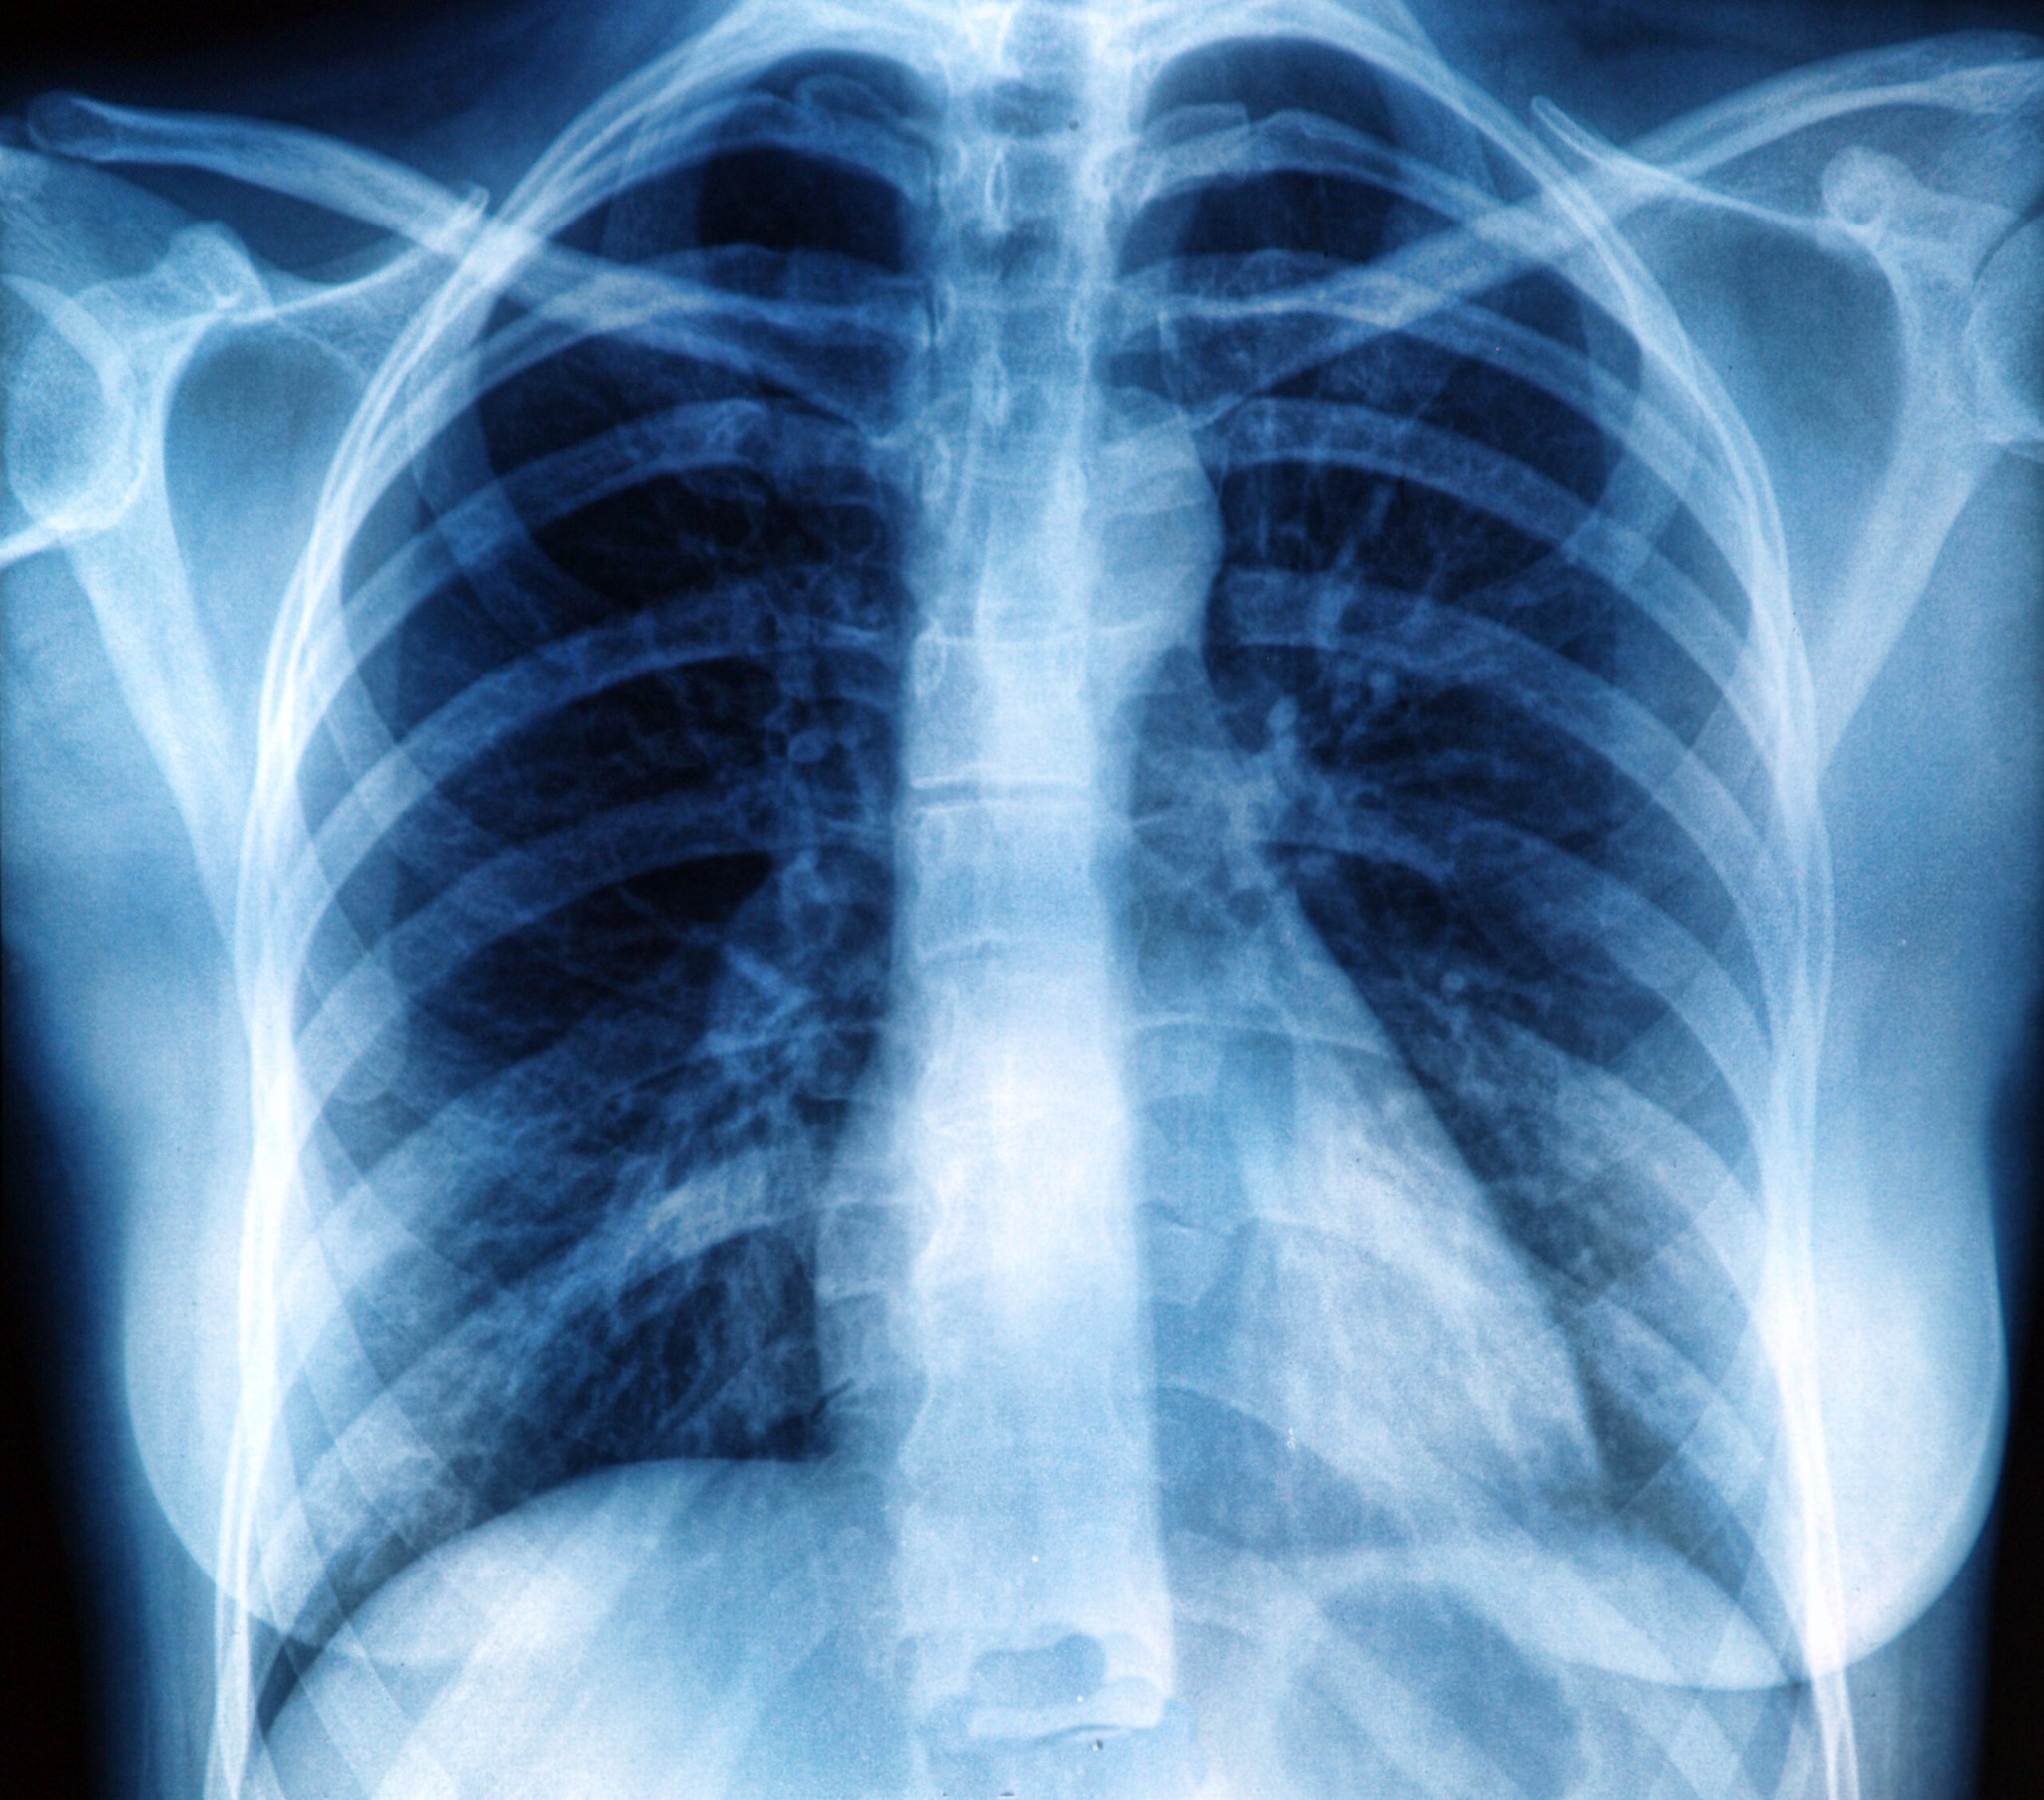

The current guidelines for lung cancer screening were established by the United States Preventive Services Task Force (USPSTF) in 2013 with pretty good reasoning: A national trial of over 50,000 former or current heavy smokers found that annual CT scans could better reduce the risk of dying from lung cancer compared with once-yearly chest x-rays. However, the guidelines are the same for everyone—even though only about 4 percent of participants in the original trial were African American.

Under these guidelines, far fewer African American smokers are eligible for lung cancer screenings, according to a new study. That may be because screening guidelines are based on the amount a person smokes or has smoked and their age. Research shows that African American smokers have different behaviors than white smokers—they tend to smoke fewer cigarettes, but have a higher risk of lung cancer. They’re also less likely to successfully quit smoking, and often are diagnosed with cancer younger than white smokers. Yet, a higher percentage of cancer cases occur in African American smokers ineligible for screening than in white smokers ineligible for screening.

The new study used cancer incidence data from nearly 50,000 smokers in the Southern Community Cohort Study. Just under 70 percent of African American smokers diagnosed with lung cancer were not eligible for screening, compared to 43 percent of white smokers diagnosed with lung cancer. African American smokers in the study were less likely to meet the benchmark for the amount smoked, and were diagnosed at a younger age.